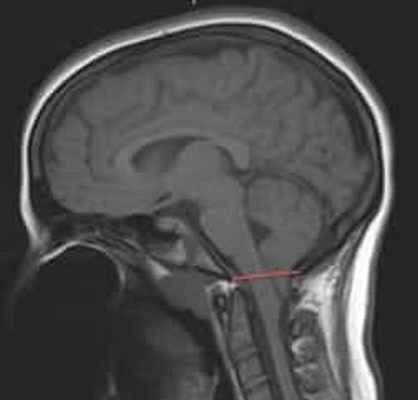

МРТ головного пациента с ААК I типа – смещение миндалин мозжечка в позвоночный канал

ниже уровня большого затылочного отверстия (более 6 мм)